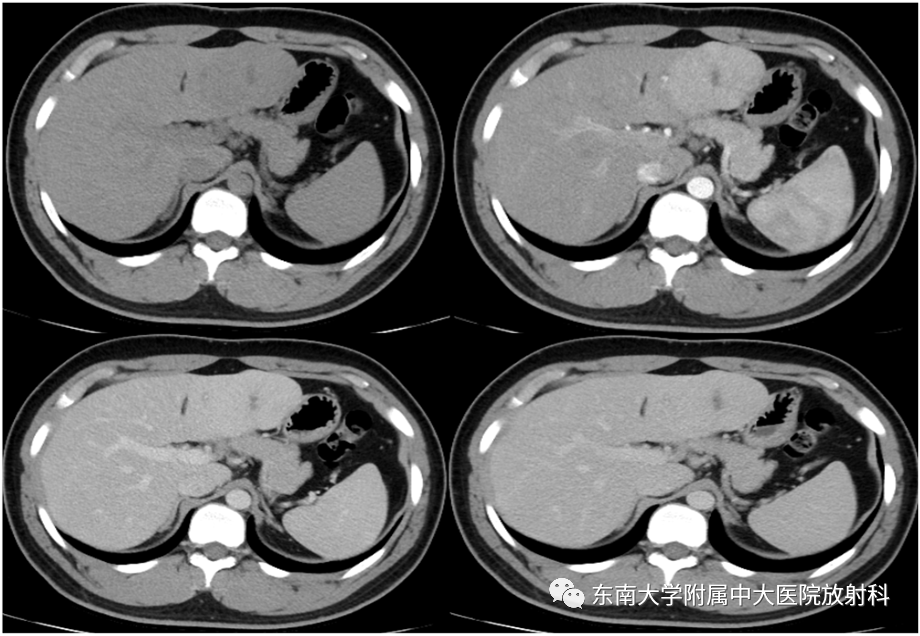

肝脏局灶性结节增生影像诊断